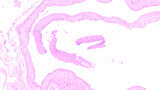

Śródkostna postać torbieli naskórkowej zlokalizowana w żuchwie – opis przypadku